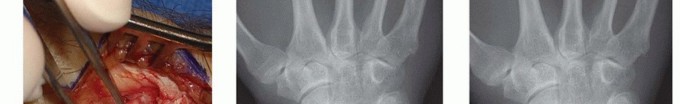

Image

The most catastrophic biomechanical complication is iatrogenic ulnar translation of the carpus. This occurs when the surgeon violates the 3-4mm safe zone, inadvertently detaching the origin of the Radioscaphocapitate (RSC) and Long Radiolunate (LRL) ligaments. Once these critical restraints are lost, the carpus invariably slides ulnarly down the slope of the radial articular surface. This leads to rapid, global radiocarpal and midcarpal arthrosis. Salvage for this disastrous complication is highly complex and typically necessitates a total wrist arthrodesis or a radiolunate arthrodesis to halt the ulnar slide and stabilize the carpus.

Conversely, under-resection of the radial styloid is a common cause of persistent postoperative pain. If the osteotomy does not adequately decompress the impingement zone, particularly during radial deviation, the patient will continue to experience mechanical symptoms. This highlights the absolute necessity of intra-operative fluoroscopic confirmation and dynamic testing. If under-resection is identified postoperatively, a revision styloidectomy may be required. Additionally, Complex Regional Pain Syndrome (CRPS) is a recognized risk following any wrist surgery; early identification and aggressive multimodal management, including sympathetic blocks and intensive hand therapy, are crucial.